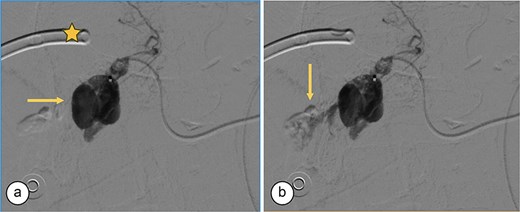

Surgical reconstruction revealed an excluded PRHD and ARHD–LHD continuity with obstruction 10 mm from the confluence. The PRHD catheter was found outside the biliary tract, so a transhepatic Nelaton catheter was placed from inside to out. A neoconfluence of PRHD with ARHD and LHD was created with a 30 mm hepaticojejunostomy. A transanastomotic Nelaton catheter and a supranastomotic ARHD catheter were left in place. Estimated blood loss: 300 cc. In the immediate postoperative period, the patient developed melena and bleeding from the Penrose drain. Cholangiography via the right percutaneous catheter showed no contrast leakage. Angio-CT revealed an 8 × 5 mm saccular lesion in the anterior right hepatic artery (Segment V), consistent with a pseudoaneurysm (Figs 1 and 2). Selective embolization with three microcoils (2 × 3 × 2.3 mm) was successfully performed (Fig. 3). The patient had a favorable recovery, with no further bleeding, and was discharged in stable condition for outpatient follow-up. Control imaging of the ARHD catheter confirmed adequate visualization of all hepatic ducts, allowing catheter removal (Fig. 4).

Angiography. (a) Saccular image consistent with a hepatic artery pseudoaneurysm (Segment V). (b) Pre-embolization image of the right hepatic artery showing contrast medium leakage (arrow) from a branch (Segment V) of the right hepatic artery. Right percutaneous catheter (star).